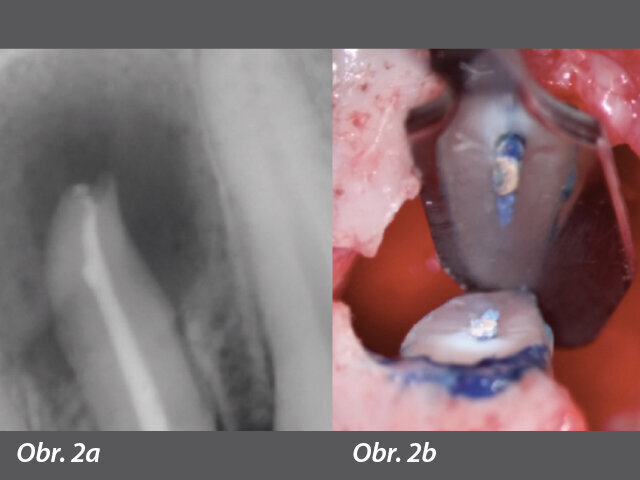

Nejvíce s tímto faktem technicky spjatá vada je použití kulatého nástroje jakéhokoli designu k vyčištění kanálku ovoidní konfigurace, což se projevuje jako nemožnost debridementu podstatného množství obsahu kanálku. Nedávná studie ukázala, že průměrná (± směrodatná) odchylka neošetřených oblastí se pohybovala od 59,6 % (± 14,9 %) do 79,9 % (± 10,3 %) pro celkovou délku kanálku a od 65,2 % (18,7 %) do 74,7 % (17,2 %) pro apikální část kanálku (obr. 2a, b).5

Axiální pohled na obturaci (mikrostrukturální replikace) ukazuje nedostatky na jednoduchém rentgenovém snímku. Významné oblasti v bukolingválním rozměru kořenového kanálku zůstaly nevyčištěny navzdory iluzornímu vzhledu na rentgenu.